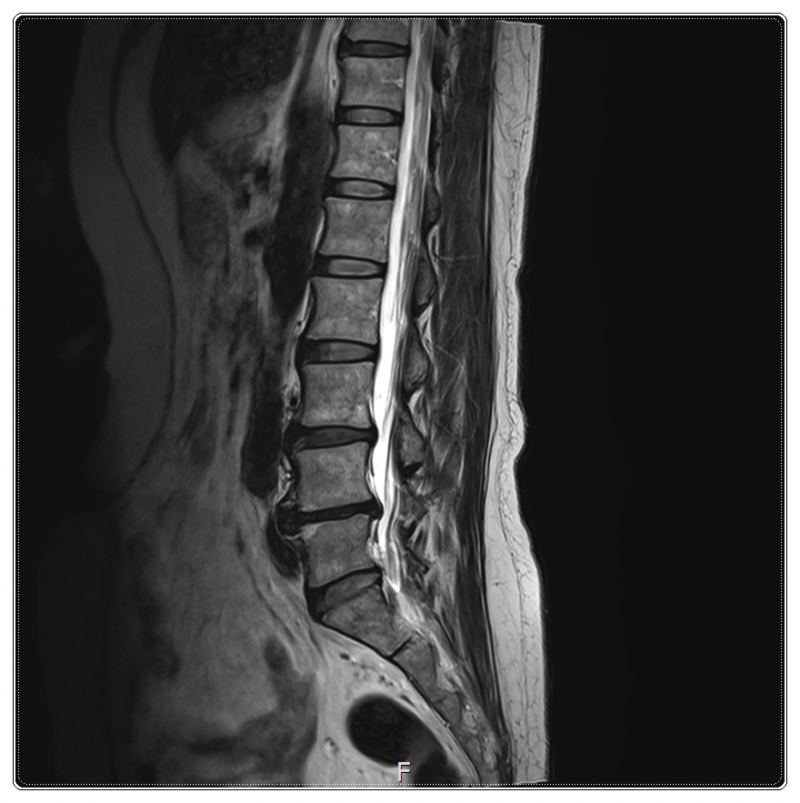

예를 들어 골반이 틀어지게 되면 척추의 균형이 무너지고, 그중에서도 요추 3·4·5번에 압력이 집중될 수 있습니다.

이러한 압력이 반복되면 주변 근육과 인대가 긴장하게 되고, 작은 충격에도 염좌가 쉽게 발생하는 상태가 되곤 하죠.

즉, 허리 통증은 결과일 수 있고, 그 원인은 골반이나 하체 정렬에 있을 가능성도 있다는 의미입니다.

골반이 앞쪽으로 기울어지는 골반전방경사가 있는 경우, 허리는 늘 과하게 젖혀진 자세를 유지하게 됩니다.

겉으로 보기에는 큰 문제가 없어 보여도, 내부에서는 허리 근육이 쉬지 못한 채 계속 긴장 상태에 놓이게 되는데요.

이렇게 되면 혈액과 기혈 순환이 원활하지 않아 염증이 발생할 가능성도 높아질 수 있습니다.